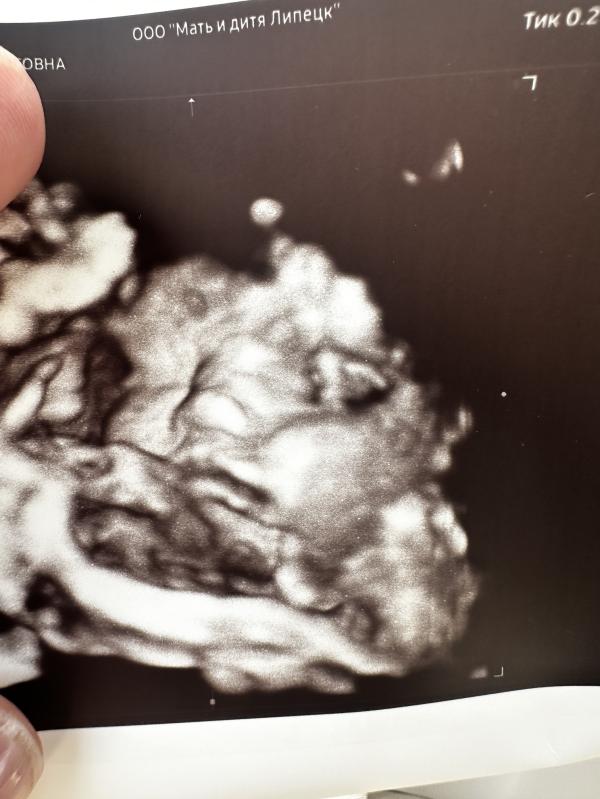

Вышла со скрининга в печали

Срок 34.5 вес 2100

Сказали вес на нижней границе нормы и не очень кровотоки. Нужен контроль узи через 2 недели отследить набор веса и ктг желательно раз в неделю.

Какой вес у ваших малышей был на таком сроке? Судя по размеру щек малышки, не похоже на маленький вес 😆